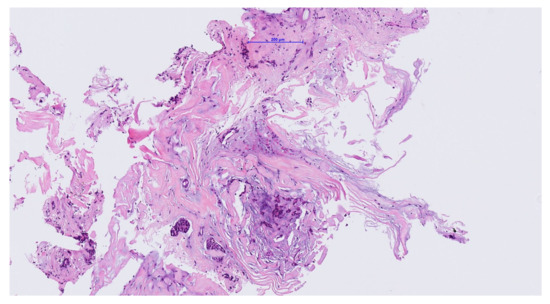

| Our case | 1/87/f | posterior | A | 13 × 10 × 6 mm | End-Exc | No rec |